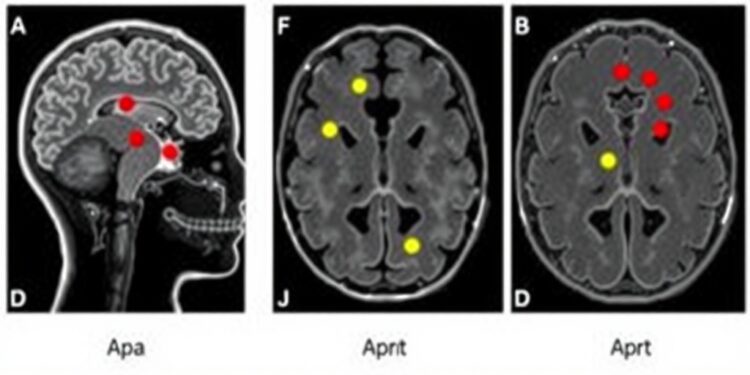

The urgency of improved detection techniques cannot be overstated, as FCD is a common structural cause of epilepsy. This condition often goes unnoticed by human radiologists; research suggests that approximately half of these subtle brain lesions are frequently missed during examinations. As a result, many patients endure unnecessary seizures and extended periods without effective treatment. In response, MELD Graph employs advanced artificial intelligence algorithms designed to recognize these elusive abnormalities on MRI scans, significantly enhancing diagnostic efficacy.

As highlighted in a recent study published in the prestigious JAMA Neurology, the performance of MELD Graph in identifying epilepsy-related brain abnormalities demonstrates a 64% detection rate of lesions that might have otherwise been overlooked. The significance of this innovation lies not only in its diagnostic accuracy but also in its potential to streamline the treatment process for countless individuals. Quicker identification of FCD allows for timely surgical interventions that can provide long-lasting relief from seizures, thus improving the quality of life for patients suffering from this debilitating condition.

A compelling case study exemplifies the tool’s potential impact; MELD Graph identified a subtle lesion in the brain of a 12-year-old boy who had been struggling with daily seizures despite being prescribed nine different anti-seizure medications. The application of this innovative tool in such instances could not only lead to timely surgeries that may dramatically alter a child’s life but also assist in more efficient surgical planning to minimize risks and reduce costs associated with prolonged hospitalizations and ineffective treatments.